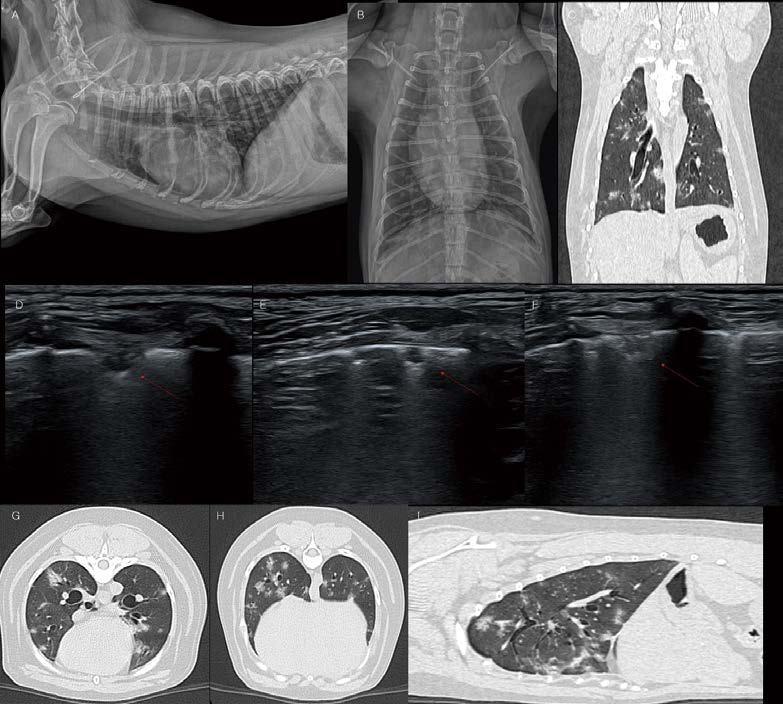

11살 중성화 수컷 Poodle이 구토, 식욕저하, 기력저하, 기침 증상으로 내원하였습니다. 혈액 검사에서 WBC 72500, CRP 14가 관찰되었습니다. 중성화 수컷임에도 불구하고 복부초음파에서 자궁과 유사한 구조물이 확인되며, pyometra 소견(고에코성의 fluid가 저류된 자궁 확장 및 벽 비후)이 관찰됩니다(A, B). 좌측 자궁각 끝에는 이질적 oval shaped 종괴가 관찰됩니다(C). 바로 수술적 제거를 실시하였고, 좌측 자궁각 끝의 종괴는 testicle로 확인되었으며, 환자는 hermaphrodite(having both male and female tissues)로 진단할 수 있었습니다(D). 환자는 수술 전 구토 증상이 있었는데, 수술 이후 오른쪽 후엽의 밀도가 유의적으로 증가하였습니다(E). 폐초음파에서 전형적인 폐렴 소견(shred sign, dynamic air bronchogram을 보이는 폐침윤 양상)이 관찰됩니다(G). 환자는 aspiration pneumonia 상태로 판단되었으며, 적극적인 응급중환자과 관리를 지속하였습니다. 그러나 2일 뒤 호흡곤란이 심해지고, 좌측 후엽의 밀도 증가 소견이 추가로 관찰됩니다(F). 폐초음파에서 우측 후엽의 폐렴 소견과 달리 좌측 후엽은 confluent B lines with irregular pleural line 소견이 관찰됩니다. Non-cardiogenic pulmonary edema(NCPE) 상태로 생각됩니다. 환자는 안타깝게도 자궁축농증, aspiration pneumonia의 전신 염증성 질환에 이차적으로 NCPE가 발생했을 것으로 생각되며, 개선되지 못하고 3일 후 사망하였습니다.

Aspiration pneumonia는 aspiration 이후 24시간까지도 흉부방사선 검사에서 나타나지 않을 수 있습니다. 이 환자도 술 전 흉부방사선 검사에서 유의적 이상 소견이 관찰되지 않았으나, 수술 이후 우측 후엽의 폐렴 소견이 관찰되었습니다. 또한 Aspiration pneumonia는 초반에 정상 체온, 정상 lung sound, 정상 호흡수를 보일 수 있다고 알려져 있으며, 인지를 못하는 과정에서 빠르게 sepsis, acute respiratory distress syndrome, multiple organ failure까지 진행될 수도 있다고 알려져 있습니다. NCPE의 영상학적 특징을 이 환자에서 잘 관찰할 수 있습니다. NCPE는 흉부방사선 검사에서 central bat-wing pattern(peripheral air sparing)이 관찰될 수 있는데, center쪽에 가까울수록 밀도가 높고, 말초로 갈수록 fade out되는 경향이 있습니다. 이 환자의 흉부방사선 좌측 후엽에서도 전형적인 NCPE의 peripheral air sparing 소견이 관찰됩니다. 또한 NCPE의 폐초음파 검사에서는 cardiogenic pulmonary edema와 비교 시 상대적으로 thickened/uneven pleural line이 관찰될 수 있으며, Inhomogeneous lung tissue with spared area가 관찰될 수 있습니다. 이 환자의 폐초음파 검사에서도 다소 불규칙한 pleural line이 관찰됩니다.